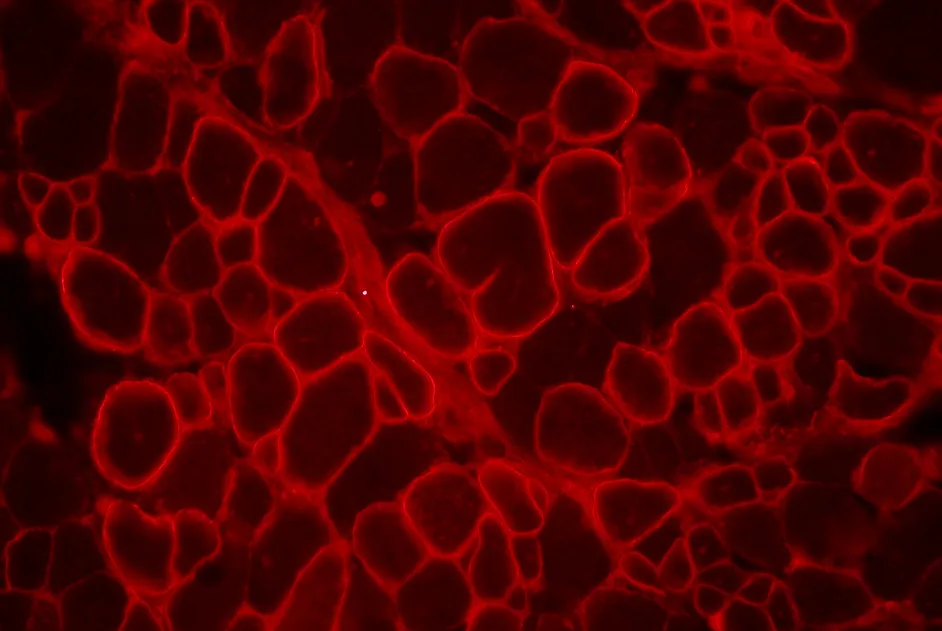

L’étude génétique des 26 membres d’une famille atteinte d'une forme d'amyotrophie spinale distale, la neuropathie motrice héréditaire distale de type VII, a mis en évidence une anomalie du gène SLC5A7. Ce gène code un composant majeur pour la synthèse et la libération de l’acétylcholine dans la jonction neuromusculaire. Cette découverte, plutôt inattendue, élargit le spectre des désordres qui sont associés à un dysfonctionnement de la jonction neuromusculaire.